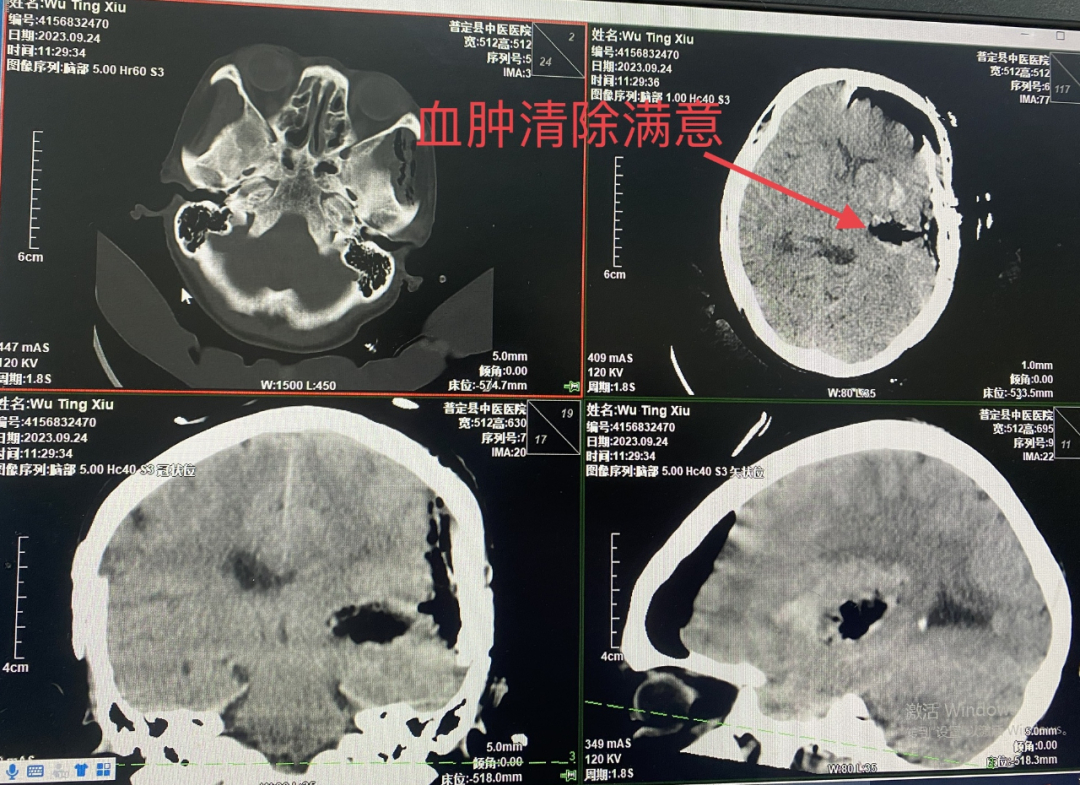

经过充分的术前讨论,制定详细手术方案,完善术前检查后,为患者行小切口小骨窗开颅血肿清除术,术中予避开神经功能区颞中回皮质造瘘长约1.5cm,深约1.5cm见血肿,术中减少脑组织牵拉,精准止血,减少电刀灼烧,清除血肿满意后还纳骨瓣,麻醉复苏后患者意识清醒,安返病房。术后6小时复查头颅CT提示血肿清除,未见颅内继发出血,血肿腔周围无明显水肿,手术效果良好,在科室医务人员的精心照顾下,患者日渐好转,于近日出院。

术后6小时CT